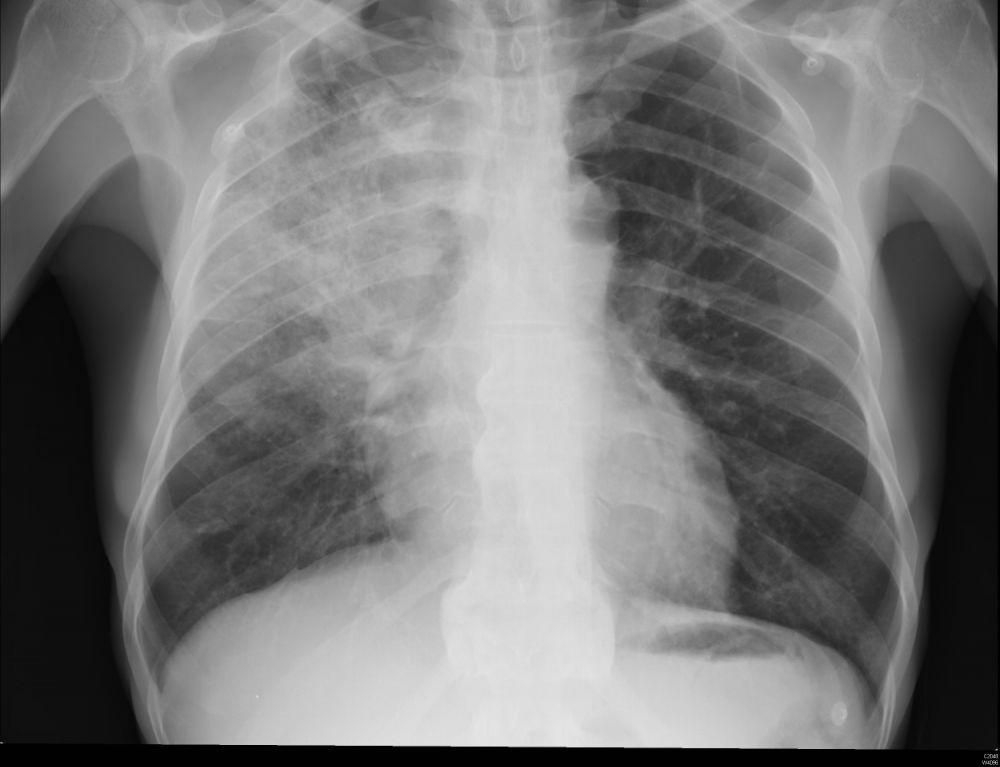

Pneumonia adalah infeksi yang menyerang kantung udara kecil di paru-paru (alveoli). Kantung-kantung ini bisa mengandung nanah atau cairan, sehingga menyebabkan penyakit ringan hingga berat. Tingkat keparahan penyakit ini sangat bergantung pada faktor-faktor seperti usia dan jenis pneumonia yang dialami.

Mengetahui jenis pneumonia yang dimiliki sangat penting agar dapat mendapatkan perawatan yang tepat. Berbagai jenis pneumonia memerlukan pengobatan yang berbeda-beda. Misalnya, satu kelompok bakteri penyebab pneumonia mungkin tidak merespons antibiotik yang sama dengan kelompok lain. Selain itu, antibiotik tidak akan efektif jika penyebab pneumonia disebabkan oleh virus atau beberapa penyebab lain yang lebih jarang.

Dengan mengetahui jenis pneumonia, dokter dapat merencanakan pengobatan yang sesuai. Pneumonia dikelompokkan dalam tiga kategori besar, yaitu pneumonia berbasis bakteri, infeksi jamur, dan virus.